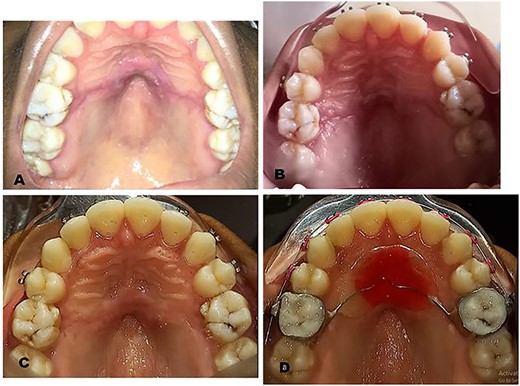

The surgical operation was performed using local anesthesia (LA). Two LA cartridges containing 2% lidocaine were administered on the palate using the subperiosteal infiltration technique. Incision was made on the palatal mucosa following the curvature of the Nance appliance using a No. 15 surgical blade. A partial thickness palatal mucosae flap was raised using a periosteal elevator to expose the buried stainless steel wire and clear acrylic palatal button of the Nance appliance (Fig. 2A). Molar bands on teeth 16 and 26 were removed using a band remover and the periosteal elevator was used to deliver the Nance appliance out of the palatal mucosa (Fig. 2B). The raised flap was repositioned (Fig. 2C) and sutured using black silk suture (Fig. 2D) and hemostasis was achieved by pressure application (patient was asked to bite on gauze for 5 min). The patient was placed on 500 mg amoxicillin, 400 mg metronidazole and 400 mg ibuprofen three times daily for 5 days postoperatively. Postoperative warm saline mouth rinse eight times daily for 2 weeks was also recommended. The patient was followed up 24 h postoperatively (PO), 7 days PO (Fig. 3A), 2 weeks PO (Fig. 3B) and 4 weeks PO (Fig. 3C). Sutures were removed 7 days PO. The patient’s postoperative course was uneventful. A new Nance palatal arch appliance with 0.9 mm hard stainless steel wire loops and the tinted acrylic button was fabricated and patient was fitted with the new Nance appliance 6 weeks PO (Fig. 3D). The patient continued to be on regular follow-up and received further dental and orthodontic treatment.

Postoperative clinical photographs: (A) One week postoperative photograph after suture removal. (B) Two weeks postoperative photograph. (C) Four weeks postoperative photograph. (D) Six weeks postoperative photograph after fitting of new Nance appliance.